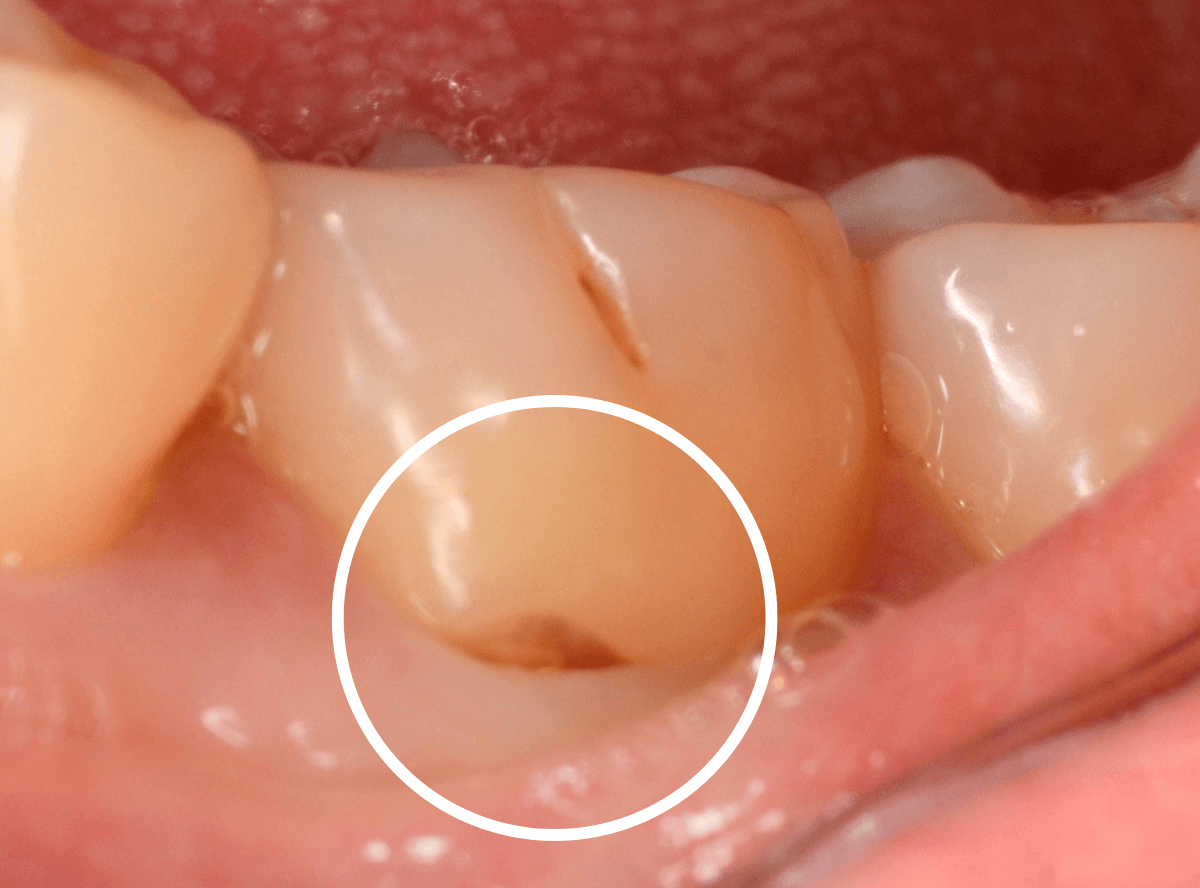

Case.4

今回は「奥歯がしみる」という訴えで来院された患者さんのケースです。

知覚過敏の方は歯の側面がしみるケースが多いですが、今回は側面もしみるが、かみ合わせの面(咬合面)もしみるといいます。

しみる歯を拝見して「ちょっとこれは難しいケースかもしれないな」と思いました。

さて、なにが難しいかといいますと、

赤線の部分、歯の溝にあたる部分がかけてるというよりも、不自然に鋭角にえぐれている状態です。

くいしばりなどかみ合わせの力がここに不自然に集中してる可能性が高く、「何かスポーツなどされてますか?」とやんわりお聞きすると、心当たりがあるのか「職場で重い物を持ってくいしばる事が多いです」との事でした。

レントゲン写真で歯を確認します。

特に中に異常はなさそうですが、油断はできません。

このように大きな力がかかった歯にはレントゲンや見えない傷がついてたりする事もあります。

すると、不定期にしみや不快感が起こる事もあり、原因がわからず途方に暮れてしまう事もあるのです。

今回は幸運にもえぐれている部分にレジンを薄くつめる事で症状はかなり緩和されましたが、かみ合わせで短期でレジンが剥がれてしまう事も大いに考えられます。

できれば、マウスピースを作製し、日中も歯を保護してほしいですが、仕事中は難しいそうです。。。

状況を説明し、定期的に経過観察に来院してもらう事になりました。